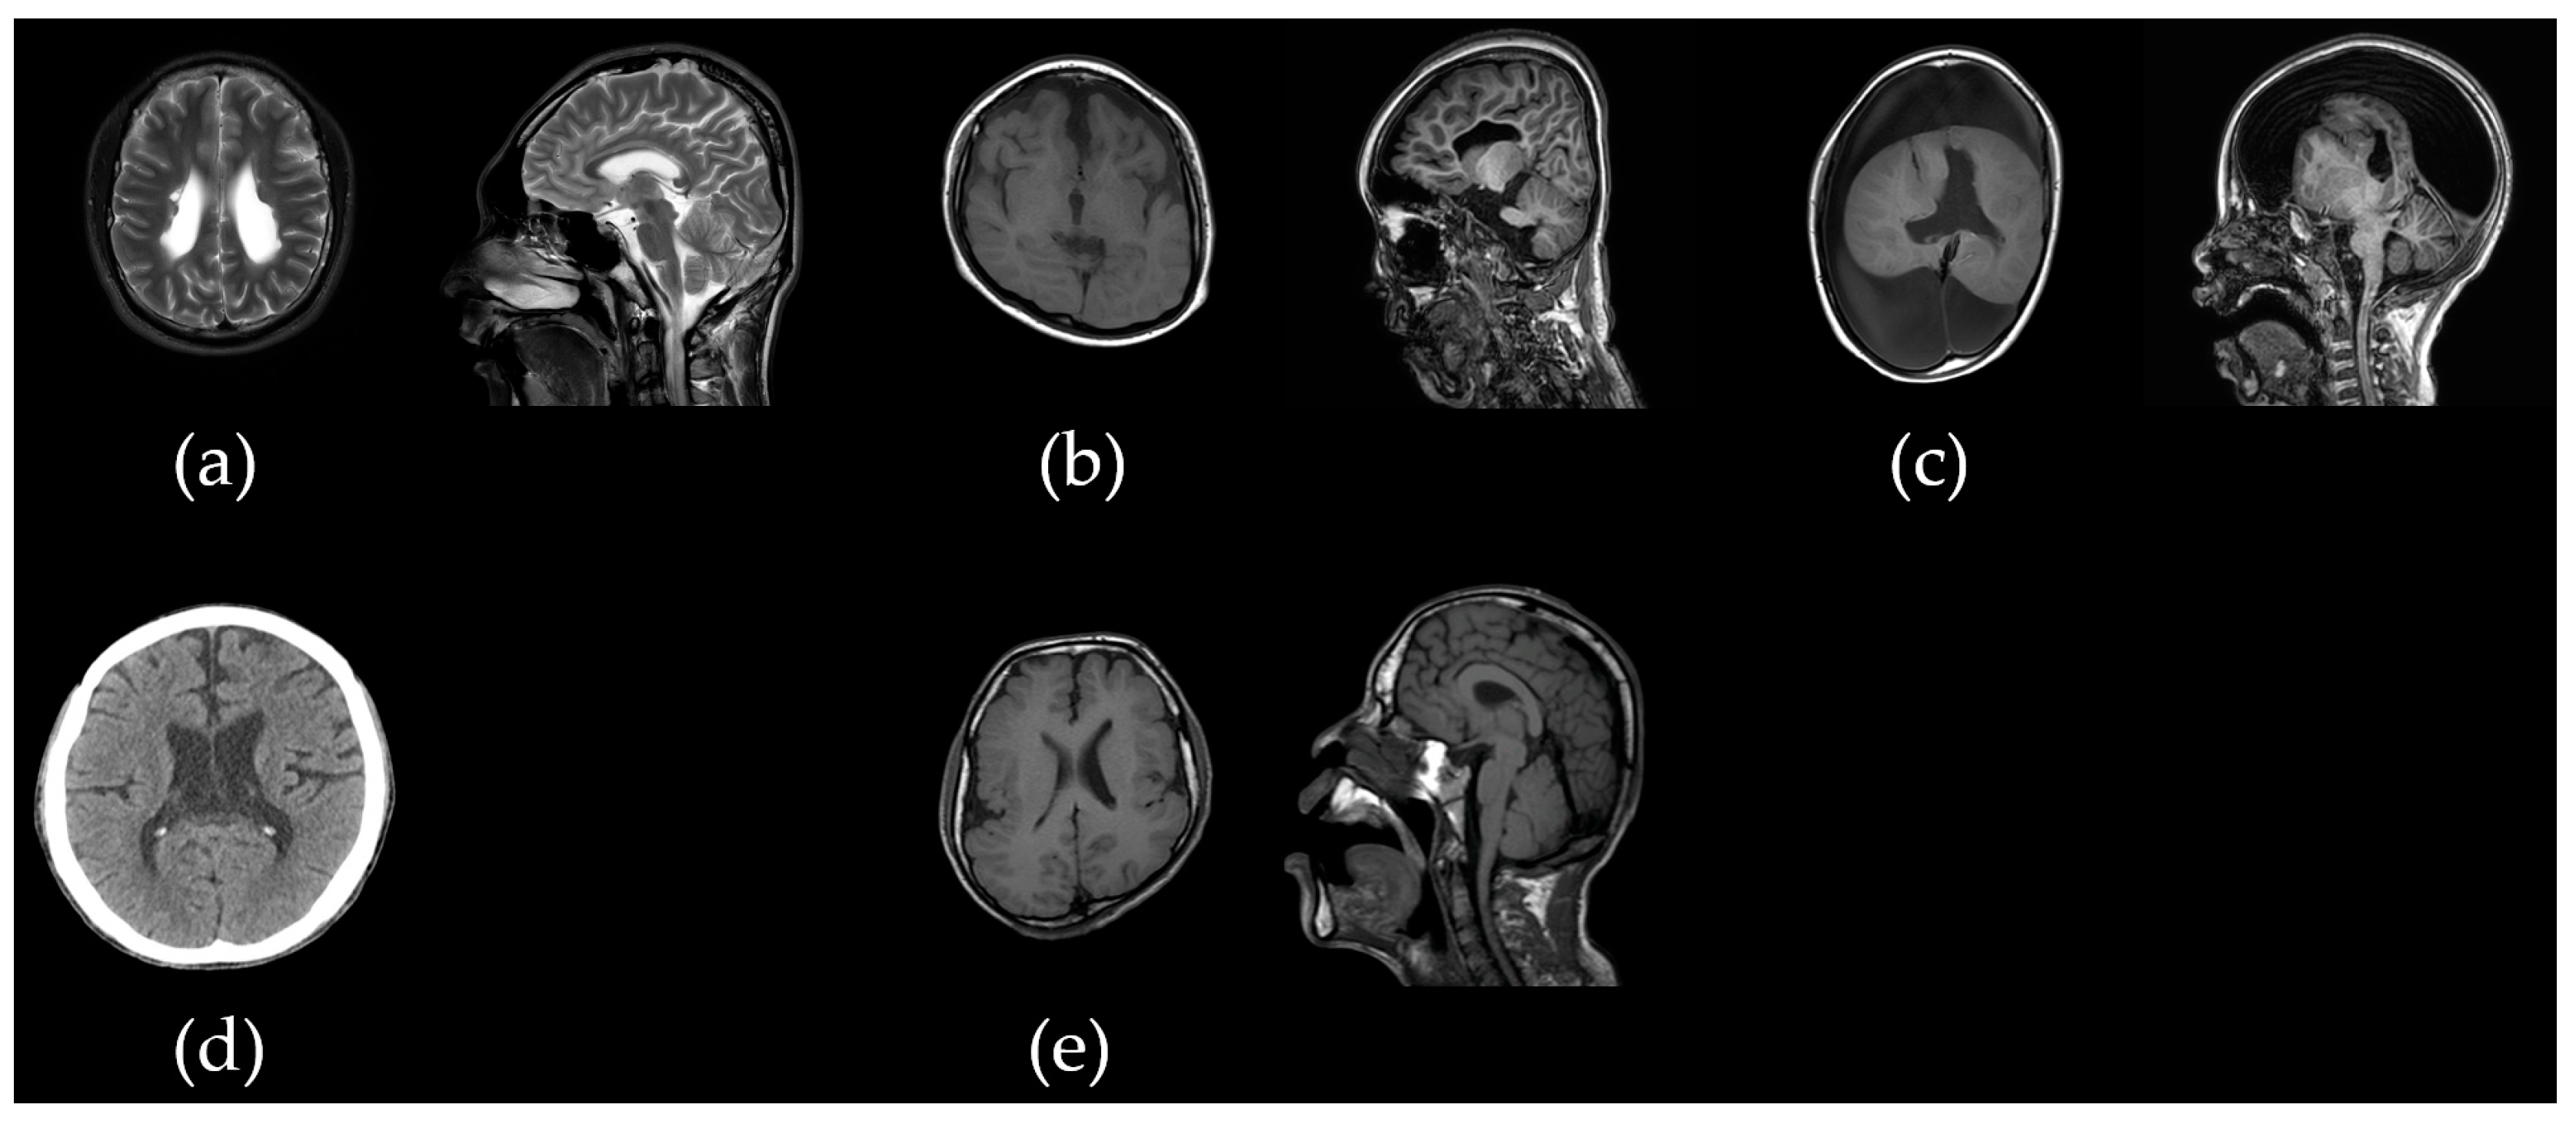

| Patient | S/A (y) | GA/BW | CP Types | GMFCS | ID | Epi/OA | Other Comorbidities | Brain MRI |

|---|---|---|---|---|---|---|---|---|

| acp01k | F/13 | 38 wks/3 kg | SQ | V | Profound | +/1 mo | NH, microcephaly | Normal |

| acp02s | M/21 | 29+5 wks/1.42 kg | SQ | V | Severe | +/20 y | None | Periventricular leukomalacia (grade II) |

| acp03k | F/15 | 38 wks/3 kg | SQ | V | Profound | +/12 mo | None | Frontotemporal atrophy with demyelinating changes |

| acp04m | F/39 | 38 wks/3 kg | Athetoid | II | Normal | −/− | None | Normal |

| acp05y | M/9 | 36 wks/2.5 kg | SQ | V | Profound | +/2 mo | None | Schizencephaly with associated callosal agenesis, hydranencephaly |

| acp06l | M/18 | 40 wks/3.36 kg | SD | V | Severe | −/− | NH | Normal |

| acp07l | M/20 | 37 wks/2.9 kg | SQ | V | Profound | +/16 y | NH | Normal |

| acp08p | M/17 | 33 wks/2.56 kg | SQ | V | Profound | −/− | NH, cryptorchidism, facial dysmorphism, thin and long fingers | Widening of the side ventricles |

| acp09k | M/25 | 41 wks/3 kg | SQ | V | Profound | +/25 y | NH, cleft palate | Schizencephaly with cortical dysplasia |

| acp10k | F/8 | 39 wks/3.5 kg | SD | III | Mild | +/7 y | SNHL, ataxia | Normal |